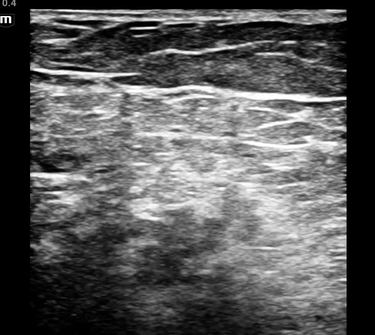

• This patient’s anatomy was not as clear as the above example images, but below are the clips from this case.

• The sciatic nerve at the split into the CPN and TN is seen just above and slightly to the right of the popliteal vessels